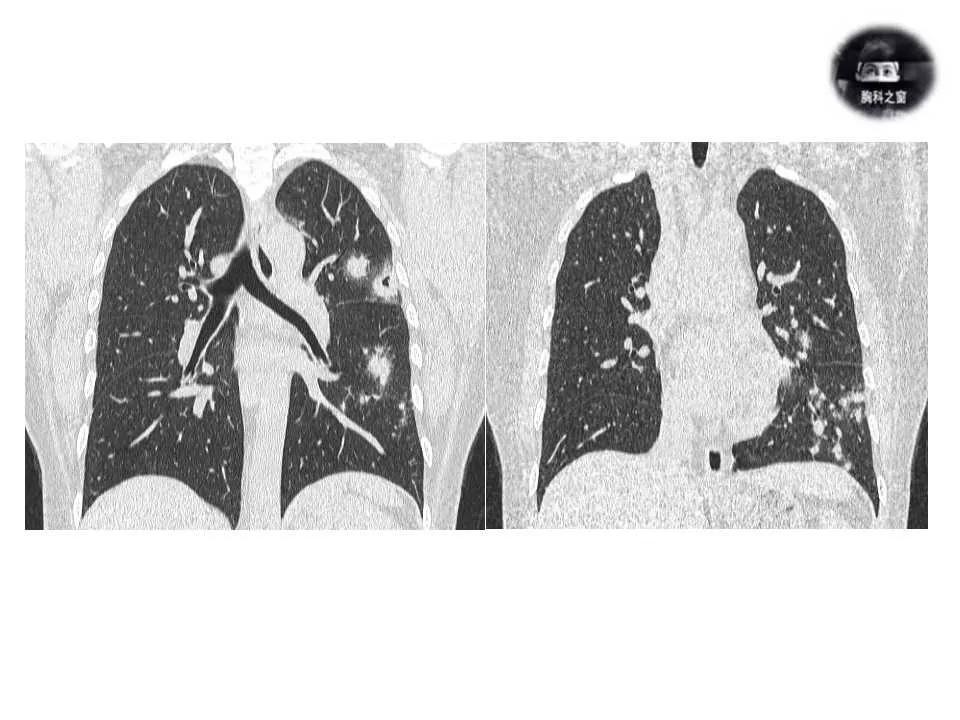

影像诊断:真菌性肺炎,隐球菌可能性大。

追问病史,有近距离接触鸽子史。隐球菌抗原(+)。

肺隐球菌病